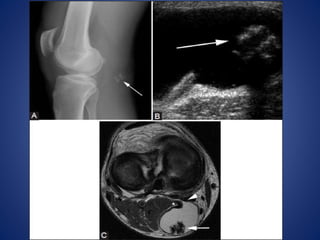

• #7 Popliteal cyst. (A) radiograph demonstrates coarse calcifications (arrow) in the popliteal fossa. (B) USG image at the level of popliteal fossa demonstrates a cystic lesion containing echogenic calcifications (arrow) with posterior acoustic shadowing. (C) Axial T2W image through right knee demonstrates the hyperintense popliteal cyst fluid arising between semimembranosus (arrowhead) tendon and medial head of gastrocnemius (asterisk), with hypointense loose bodies (arrow) layering dependently